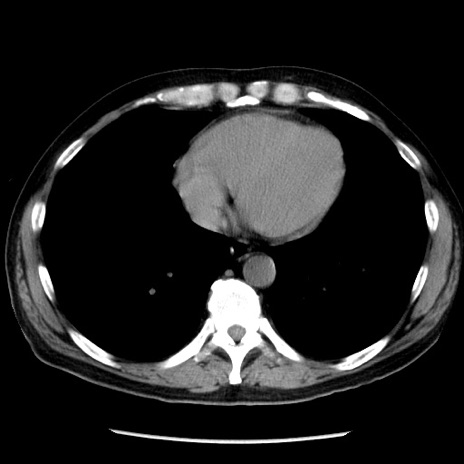

症例29(横断像)

【症例】40歳代男性

【現病歴】2日前から胃痛あり。徐々に周期的な激痛に変化した。本日になっても激痛があるため受診。

【身体所見】意識清明、BT 38-39℃台あり、腹部:膨満、やや硬、右下腹部に圧痛あり。

【データ】WBC 8500、CRP 23.26